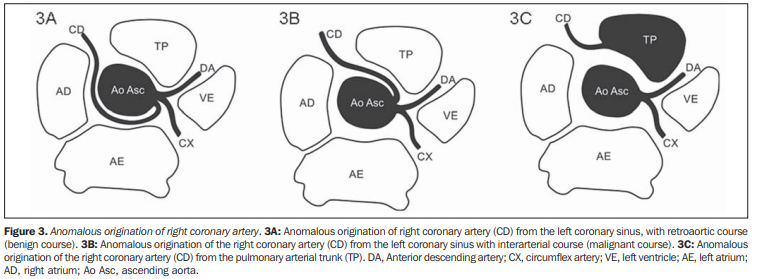

Coronaire Droite

Anomalie de naissance de la CD

- Malin = Si la CD a un trajet entre le tronc pulmonaire et l’aorte

- Naissance de la CD de la CG avec trajet inter-artériel